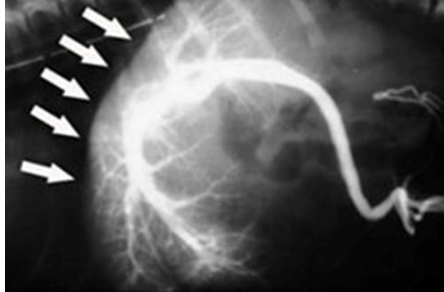

what does the radiograph show?

normal portogram showing hepatic vasculature